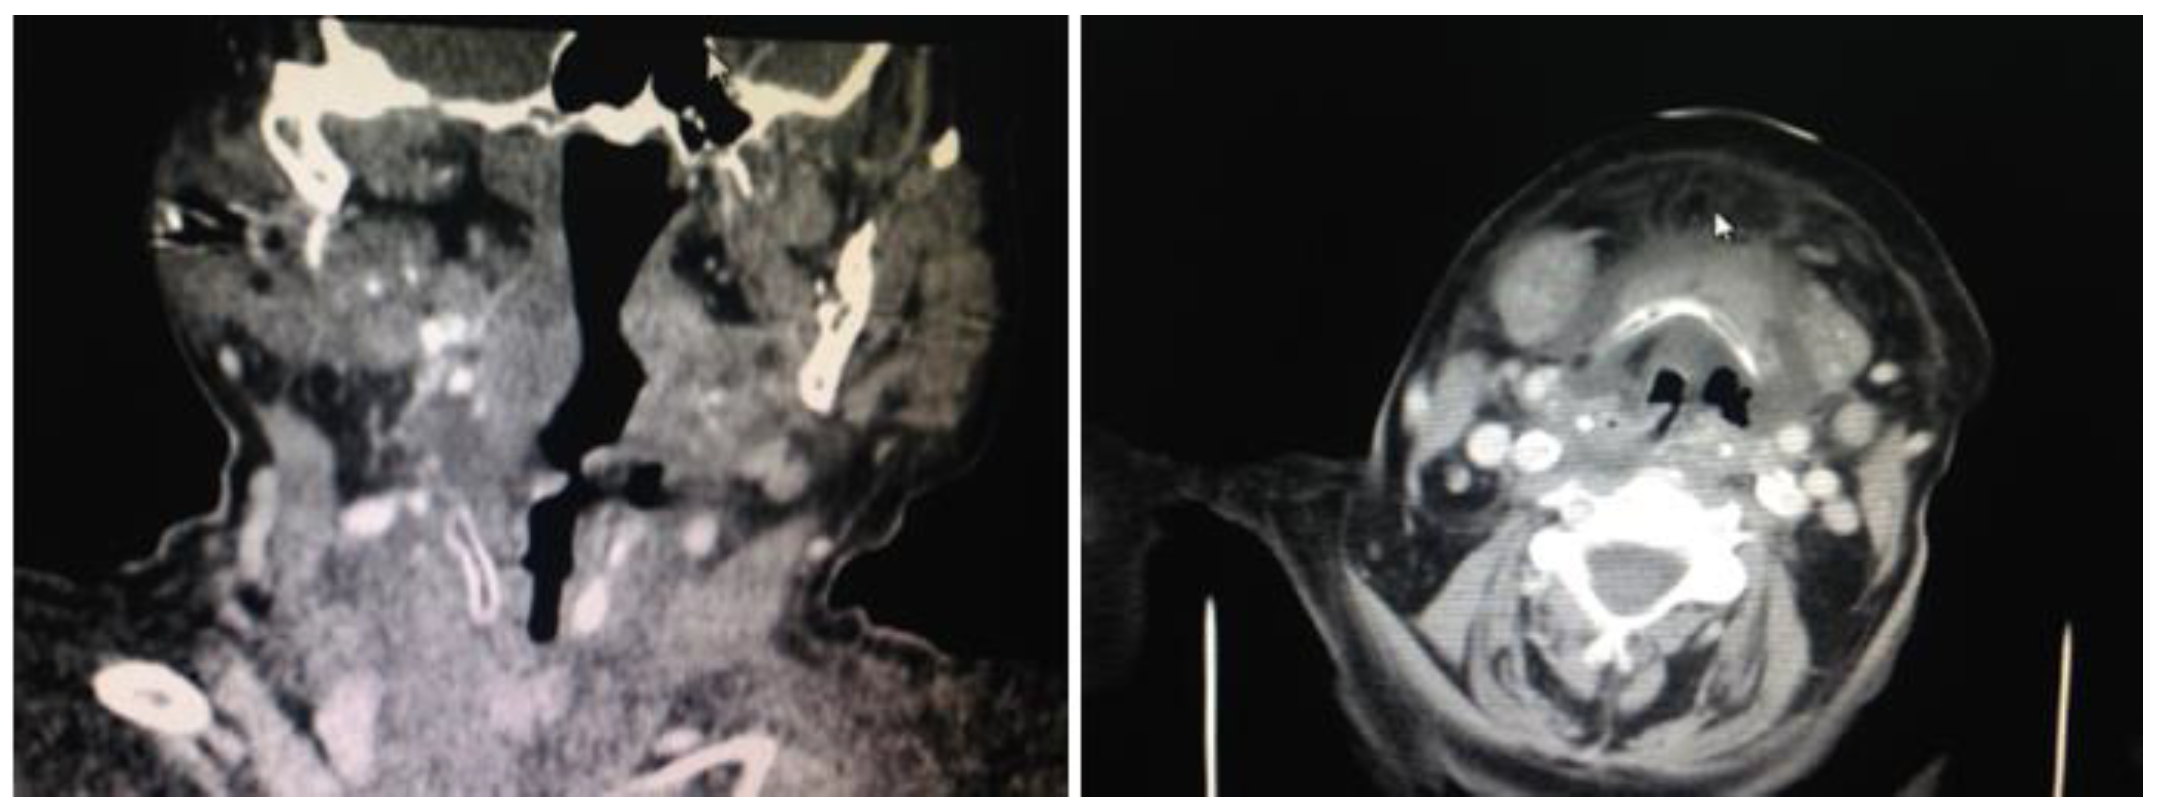

At admission the blood test revealed leukocytosis, along with kidney failure (creatinine: 2,31 mg/dl, urea: 121,98 mg/dl, creatinine clearance: 22 ml/min/1,73m2 according to MDRD), as well as oscillatory modification of sugar levels (Figure 1, Figure 2 and Figure 3).

Paraclinical examination using imaging studies of the cervical and thorax regions revealed consistent collection surrounding the pharynx and the prevertebral space. The pharynx cavity had a reduced asymmetrical lumen. The subcutaneous tissue was infiltrated with extensive edema. Multiple lymph nodes were visible on the left submandibular space with diameters up to 15 mm. Left submandibular gland was infiltrated. The native and contrast thorax CT revealed normally expanded lungs, no spontaneous visible focal lesions or post intravenous contrast, no pleural collections or effusions, and no mediastinal adenopathy of pathological dimensions. The CT diagnosis was possible and revealed parapharynx and submental phlegmon (Figure 4).

Figure 4. CT cross-sections of the neck region showing the extension of the neck deep space collection.